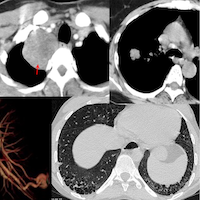

The sentence “please correlate clinically” is perhaps the worst line in radiology practice, because it sends a message to the referring doctor that we are not physicians and we are not part of the patient’s management team, but are turfing the onus of the diagnosis onto them. Yes when we lack certain clinical data, we can word the report to reflect that, for e.g. in a patient with ground-glass attenuation, we can say that “this is most likely suggestive of hypersensitivity pneumonitis, provided the patient is not immunocompromised or an ever-smoker or in failure”, because we were unable to get the appropriate history. But to write, “ground glass attenuation seen, ?hypersensitivity pneumonitis, please correlate clinically”, betrays a sense of not wanting to be involved.

I went onto say then that this is the reason why teleradiology practiced as a means of just reading scans without being part of a patient management team is rubbish. Over the years I have believed and still believe that while AI can replace some image-readers, it will not replace radiologists who are clinicians and keep trying to answer the question, “why”.